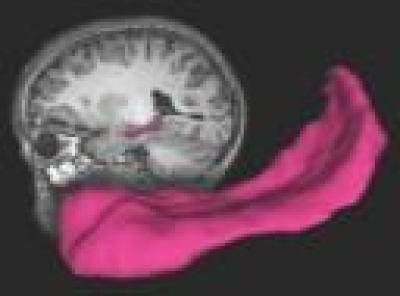

School-age children whose mothers nurtured them early in life have brains with a larger hippocampus, a key structure important to learning, memory and response to stress.

For the current study, the researchers conducted brain scans on 92 of the children who had had symptoms of depression or were mentally healthy when they were studied as preschoolers. The imaging revealed that children without depression who had been nurtured had a hippocampus almost 10 percent larger that children whose mothers were not as nurturing.

"For years studies have underscored the importance of an early, nurturing environment for good, healthy outcomes for children," Luby says. "But most of those studies have looked at psychosocial factors or school performance. This study, to my knowledge, is the first that actually shows an anatomical change in the brain, which really provides validation for the very large body of early childhood development literature that had been highlighting the importance of early parenting and nurturing. Having a hippocampus that's almost 10 percent larger just provides concrete evidence of nurturing's powerful effect."

The fact that the researchers found a larger hippocampus in the healthy children who were nurtured is striking, Luby says, because the hippocampus is such an important brain structure.

When the body faces stresses, the brain activates the autonomic nervous system, an involuntary system of nerves that controls the release of stress hormones. Those hormones help us cope with stress by increasing the heart rate and helping the body adapt. The hippocampus is the main brain structure involved in that response. It's also key in learning and memory, and larger volumes would suggest a link to improved performance in school, among other things.